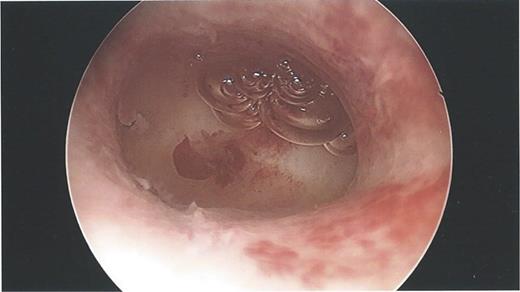

During the hysteroscopy 4 weeks later there was no evidence of an IUCD into the uterine cavity and no evidence of a perforation site in the uterus (Fig. 1). A laparoscopy followed, locating the coil threads deep in the Pouch of Douglas, with the IUCD perforating through the sigmoid colon into the lumen (Fig. 2). The IUCD was retrieved laparoscopically and the defect in the sigmoid colon was repaired by stapling the tear (Fig. 3).

Hysteroscopy showing a normal endometrial cavity, no evidence of IUCD or site of perforation.